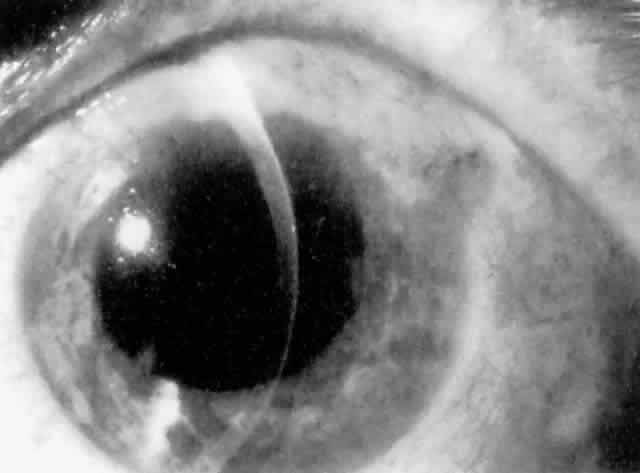

Cortical lens fragments retained in either the anterior chamber or the vitreous can also obstruct the trabecular meshwork in the form of free lens particles or macrophages swollen with lens material (Figs. 2 and 3). Glaucoma does not occur in all eyes that contain cortical remnants; the inflammatory response may be more pronounced and prolonged in eyes containing a higher amount of lens material. When inflammation is marked, keratic precipitates and sometimes a hypopyon may be present. Distinction between this sterile inflammatory endophthalmitis and infectious endophthalmitis can be difficult and may depend on the initial response to therapy. The presence or absence of IOP elevation is not helpful in making this distinction because IOP may be normal or elevated in both situations.

Fig. 2. Fluffy, hydrated cortical lens fragments retained in the anterior chamber after cataract extraction, resulting in inflammation and elevated intraocular pressure.